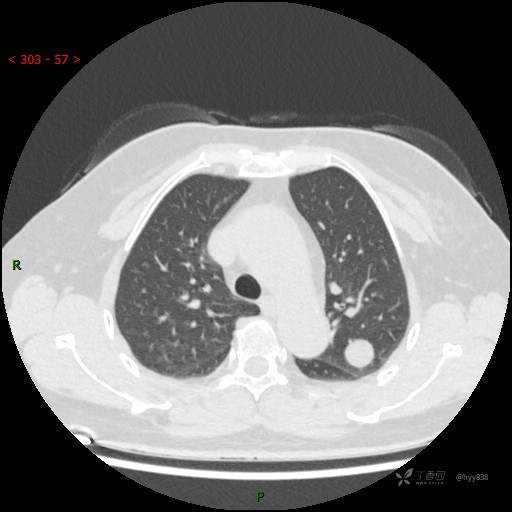

讨论:结节性质?

胸部CT平扫

各期CT值:28hu、58hu、69hu